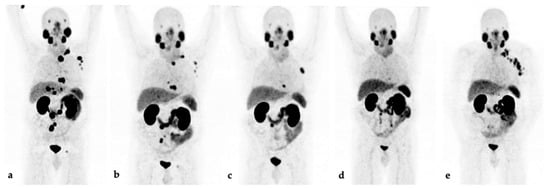

PSA decline (≥50%) after 12 weeks occurred in 12/25 (48%) patients; 6/25 (24%) remained stable. Seven (28%) patients showed PSA progression (n = 4) or died (n = 3) within 12 weeks. Imaging assessment showed PR in 11/25 (44%) patients, and 4 patients (16%) had SD. Ten (40%) patients had PD (n = 7) or were deceased before the assessment (n = 3). An example of a disease course on 68Ga-PSMA-11 PET/CT imaging is provided in Figure 1.

Figure 1.

Maximum-intensity projections of 68Ga-PSMA-11 PET/CT imaging of a metastasized castration-resistant EOPC patient during LuPSMA-RLT and follow-up. (a) At baseline, PSA: 69.3 ng/mL; (b) after three cycles, PSA at 12 weeks: 6.8 ng/mL; (c) after six cycles, PSA: 2.4 ng/mL; (d) after eight cycles, PSA: 0.3 ng/mL; (e) restaging 7 months later, PSA: 15.9 ng/mL.